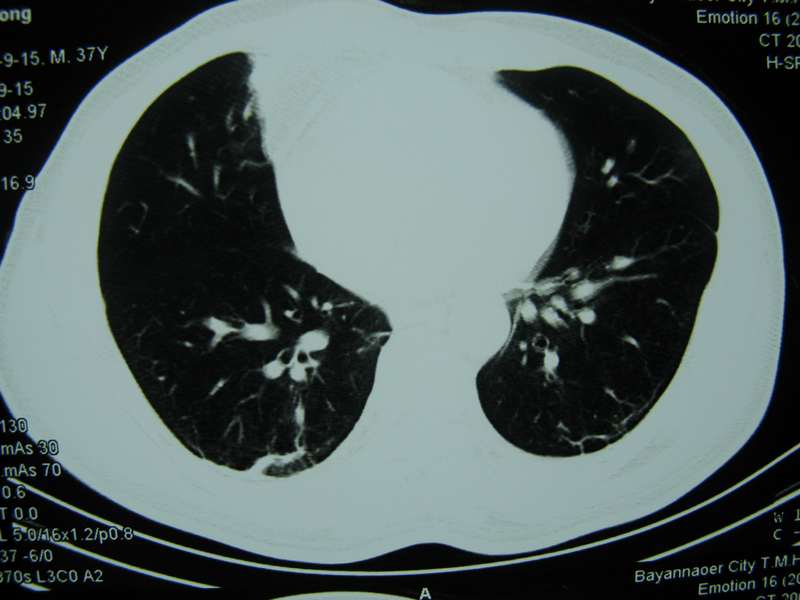

男,37岁,主述胸疼厉害,无咳嗽,无发热,血象也不高,病灶内ct值脂肪密度,右侧胸腔内少量积液,同道们考虑什么?谢谢!

两肺下叶基底段纤维灶,右肺下叶基底背侧相应胸膜肥厚,右肺中叶内侧段部分不张。前中下纵隔团块状脂肪影,随访除外胸腺脂肪瘤。